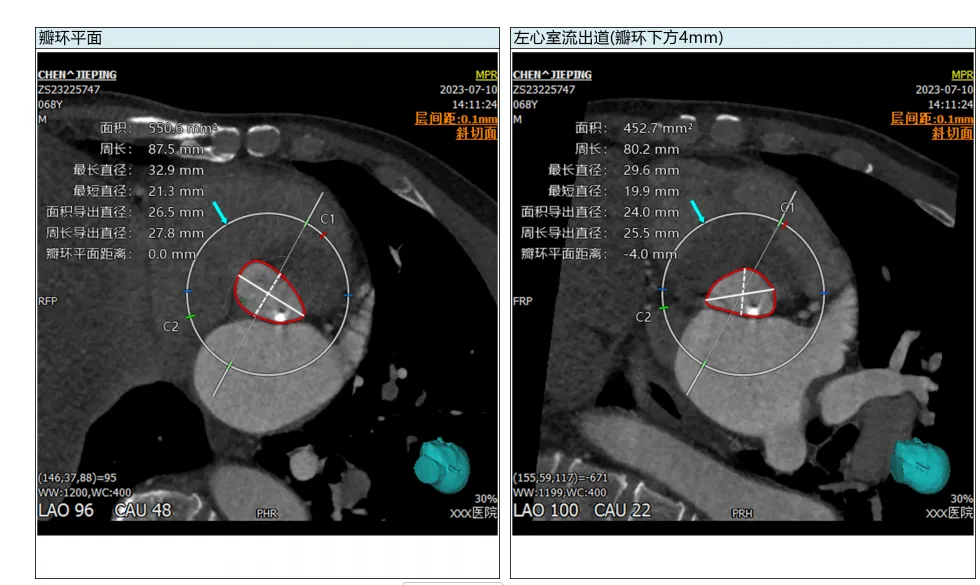

• 术前规划:基于 CT/MRI/ 超声影像完成心脏结构 3D 重建、关键参数自动化测量、植入体型号匹配、入路评估;

1. 影像自动化分析:基于深度学习实现心脏结构自动分割、参数精准测量,替代传统人工手动分析,核心解决效率与标准化问题;

• 核心产品与功能:核心产品为3mensio Structural Heart 工作站,分为结构心与血管两大模块,其中结构心模块覆盖 TAVR/TMVR/PPVI/LAAO 等全术式的术前规划,核心功能包括:主动脉根部 / 二尖瓣 / 左心耳等结构的自动化分割与精准测量、虚拟瓣膜植入、钙化积分评估、入路血管分析,支持非增强扫描融合分析。